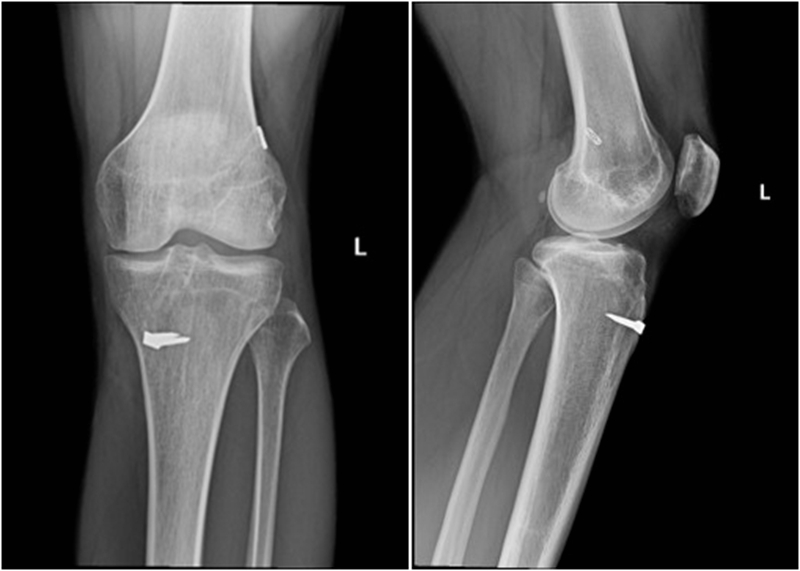

术前X线

术后X线